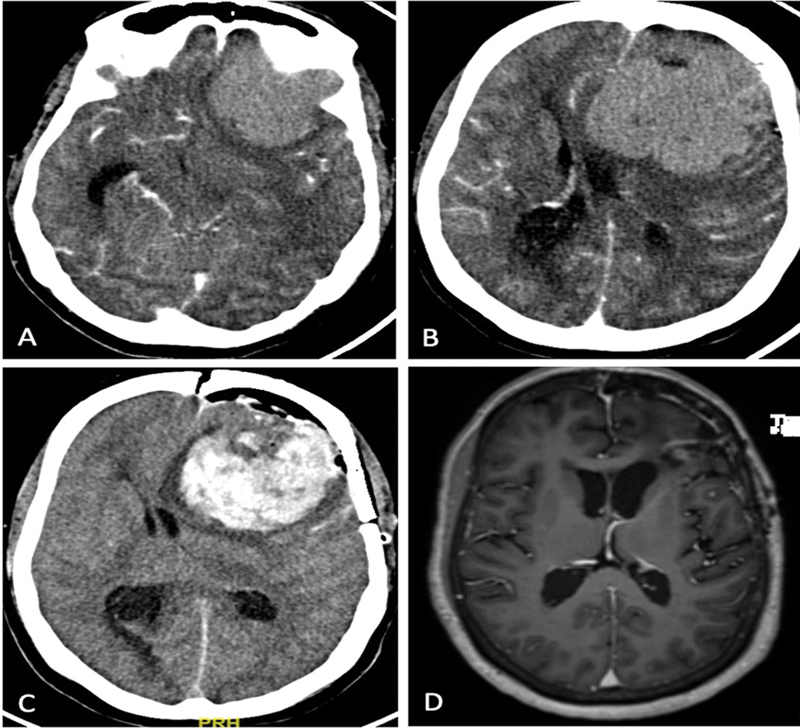

目的 颅内脑膜瘤占所有脑肿瘤的三分之一,是全世界神经外科手术最常见的适应症之一。大多数脑膜瘤症状不明显,病程较长。然而,有关脑膜瘤急诊手术结果的数据却很有限。本研究旨在介绍我们对急诊脑膜瘤患者进行紧急手术干预的经验。我们还分析了影响早期神经系统预后和并发症的因素。材料和方法 回顾性分析了 2015 年 1 月至 2019 年 12 月间所有非选择性急诊脑膜瘤手术。记录患者的人口统计学、临床和放射学细节,以便进行分析。手术过程、并发症和随访结果也包括在内,以便进行统计比较。结果 44 名患者符合研究条件,平均年龄(49.4±13.4)岁。患者的格拉斯哥昏迷量表(GCS)平均值为 13;47.7% 的病例出现感觉改变。最常见的病变位置是凸面(25 例,占 56.8%),平均肿瘤体积为 74.1 ± 36.5 mL。16例患者(36.4%)出现肿瘤周围水肿和肿块效应。随访 3 个月时的平均 Karnofsky 表情状态为 89.3 ± 18.2。患者年龄和肿瘤大小对预后没有影响。出现 GCS(P 0.03)和术后并发症(OR 25.71,CI 2.65-249.2,P 0.001)与不良预后有关。虽然没有统计学意义,但肿瘤分级较低也与较差的临床预后有关(P 0.20)。结论 脑膜瘤急诊手术的疗效和并发症发生率与常规择期手术相当。II/III 级脑膜瘤更有可能出现急性神经功能恶化,预后相对较差。在我们的研究中,GCS表现不佳和术后并发症是导致患者预后不佳的最关键因素。

Objective  Intracranial meningiomas constitute a third of all brain tumors and are among the most common indications for neurosurgical procedures performed worldwide. Most meningiomas present with an indolent, longstanding history. However, the data on outcomes of emergency surgeries for meningioma is limited. This study aims to present our experience of urgent surgical intervention in patients with meningiomas presenting acutely. We also analyze the factors influencing early neurological outcomes and complications. Materials and Methods  All nonelective meningioma surgeries done on an emergency basis between January 2015 and December 2019 were retrospectively reviewed. Patients' demography, clinical, and radiological details were recorded for analysis. The surgical procedure, complications, and follow-up outcomes were also included for statistical comparison. Results  Forty-four patients qualified for the study with a mean age of 49.4 ± 13.4 years. The average presenting Glasgow Coma Scale (GCS) was 13; 47.7% of cases presented with altered sensorium. The most common lesion location was convexity (25, 56.8%), and the mean tumor volume was 74.1 ± 36.5 mL. Gross peritumor edema with mass effect was seen in 16 patients (36.4%). The mean Karnofsky Performance Status at 3 months' follow-up was 89.3 ± 18.2. Patient age and tumor size did not affect outcomes. The presenting GCS of < 15 (odds ratio [OR] 8.8, confidence interval [CI] 0.95-80.72, p 0.03) and the occurrence of postoperative complications (OR 25.71, CI 2.65-249.2, p 0.001) were associated with unfavorable outcomes. Although not statistically significant, a poor tumor grade was also associated with worse clinical outcomes ( p 0.20). Conclusion  Emergency meningioma surgery has comparable outcomes and complication rates with routine elective procedures. Grade II/III meningiomas are more likely to present with acute neurological deterioration and carry a relatively worse prognosis. Poor presenting GCS and postoperative complications are the most critical factors associated with poor patient outcomes in our study.